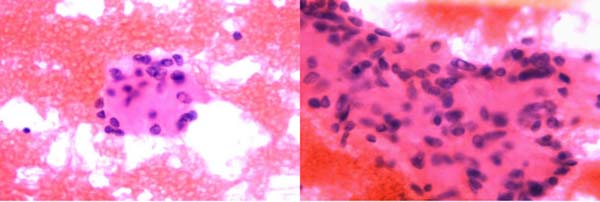

甲状腺-FNA:可见较多量甲状腺滤泡上皮细胞,排列松散或小团状,细胞核增大、拉长,核沟和核内假包涵体易见,背景中可见均质粉染透明变物质。

甲状腺-粗针活检:瘤细胞排列呈小梁状、器官样结构,细胞梭形或呈多角形,长轴垂直于基底膜,胞质丰富,嗜酸或透明,核沟及核内假包涵体易见,未见核分裂象,细胞巢间可见透明变的基底膜样物质沉积。

HTT通常表现为单侧单发有包膜的结节,界限清楚,切面实性、分叶状,灰白至淡黄色。镜下肿瘤以形成小梁状优势结构为特征,或呈实性巢状、腺泡状结构,间质富于窦状毛细血管;肿瘤细胞梭形或呈多角形,胞质丰富,嗜酸或透明,长轴垂直于基底膜,核的特征类似于PTC,核沟及核内假包涵体易见,核周可见特异性黄色小体,核分裂象罕见。瘤细胞巢间可见大量透明变的基底膜样物质沉积,PAS染色及胶原Ⅳ免疫组化染色阳性。HTT细胞核的特征与PTC有重叠,针吸细胞学易误诊为PTC,HTT细胞学示甲状腺滤泡上皮细胞丰富,围绕淀粉样透明变基质呈放射状排列,无乳头及滤泡结构,无平铺细胞片,细胞核拉长呈梭形,核膜不规则,核沟及核内假包涵体易见,胞界不清。Marina N. Nikiforova等研究表明,与PTC不同,GLIS重排在HTT中较普遍,特别是PAX8–GLIS3重排,这种融合基因导致GLIS过表达,进一步上调细胞外基质基因引起胶原沉积,从而产生镜下肿瘤组织中胶原丰富的现象。